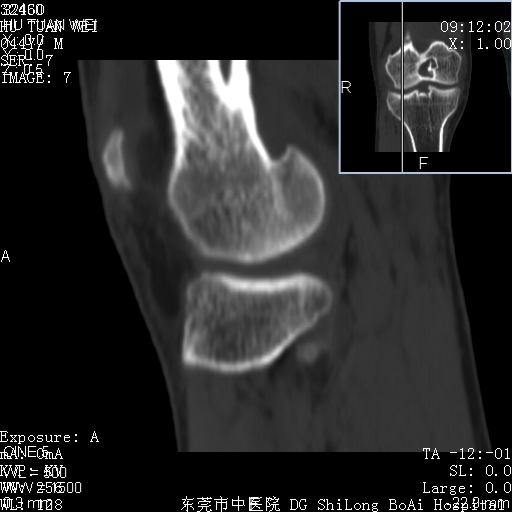

中年男性,膝韧带损伤术前检查!其他病史不清粗,不是我接手病人、且出院了!

1、股骨下段囊状膨胀性病变,边缘硬化明显,内多个残留骨棘呈多房型改变,囊腔密度较高无钙化,膝关节滑膜囊增厚,密度增高,关节腔少量积液。考虑:邻关节囊肿、退变性囊肿(软骨下囊肿)、着色性绒毛结节性滑膜炎、abc、骨巨、良性纤维组织细胞瘤等鉴。虽然年龄偏大,部位于骨端,但有外伤史,本人还是倾向于动脉瘤样骨囊肿(abc)可能性大。邻关节囊肿及软骨下囊肿次之考虑。

2、胫骨髁间棘撕脱骨折,交叉韧带损伤可能;

3、关节退行性改变。

病理结果:色素沉着绒毛结节性滑膜炎

感谢反馈病理结果!本病为慢性关节病变。以关节滑膜高度增生、绒毛结节形成伴含铁血黄素趁着为特点。病因:有炎症、肿瘤、外伤关节出血、代谢障碍、变态反应及感染等学说。增强扫描呈关节腔内单个或多个强化的软组织结节影或滑膜不规则增厚伴关节积液为本病的特征性表现。